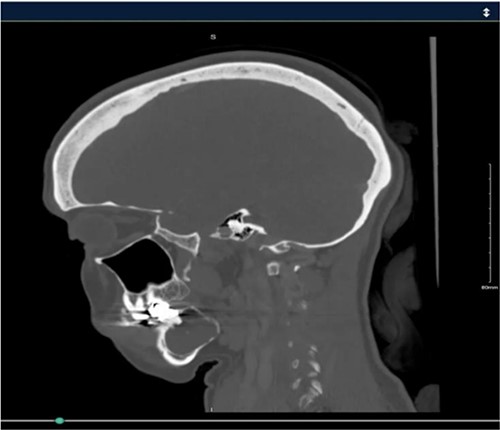

A 40-year-old woman presented with swelling on the right side of her mandible. She had completed orthodontic treatment 2 years earlier. A panoramic radiograph showed a unilocular radiolucency extending from the mandibular angle to the right first molar region (Figs 1–3).

Panoramic radiograph showing a unilocular radiolucency extending from the right mandibular angle to the right first molar region.